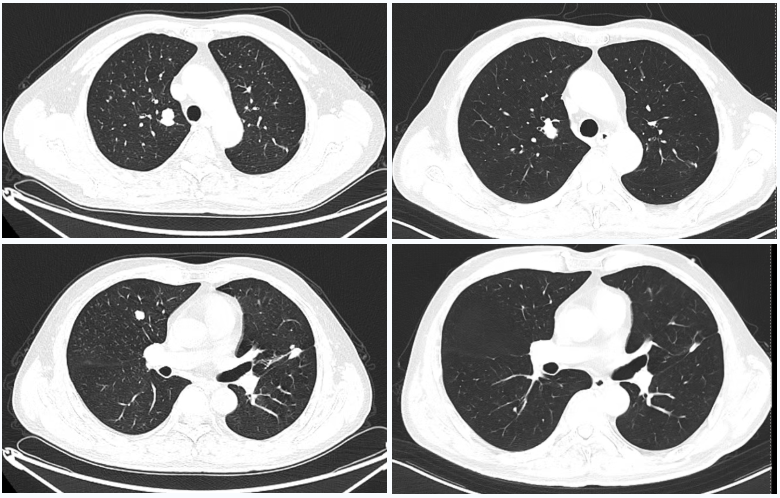

△2023年2月患者基线时CT(左)与2024年4月时CT(右)检查所见对比

患者入院并完善相关检验检查后,治疗团队评估病情并核对入排,且患者及家属有参与临床研究意愿,入组II/III期临床研究FRUSICA-2,遂于2023-02-01开始予患者呋喹替尼(5mg,qd,用2周停1周)+信迪利单抗(200mg q3w)联合治疗,患者按方案治疗并规律复查,治疗6周期后疗效评价为疾病稳定(SD),至治20周期(2024-04-03)时疗效评价达到部分缓解(PR)。此后患者继续原治疗方案,至2025-02-13时因信迪利单抗治疗满24个月,按FRUSICA-2研究要求停用免疫治疗。